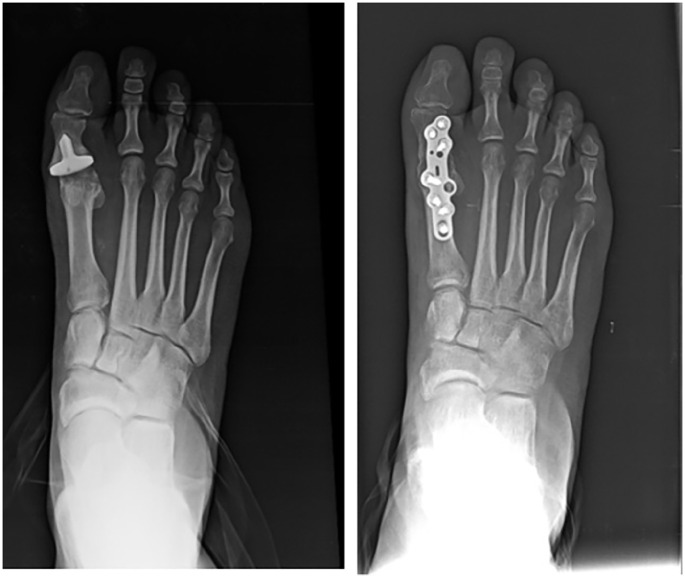

Abstract Image